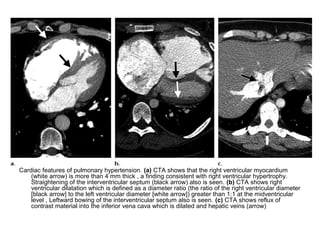

Cardiac features of pulmonary hypertension. (a) CTA shows that the right ventricular myocardium

(white arrow) is more than 4 mm thick , a finding consistent with right ventricular hypertrophy.

Straightening of the interventricular septum (black arrow) also is seen. (b) CTA shows right

ventricular dilatation which is defined as a diameter ratio (the ratio of the right ventricular diameter

[black arrow] to the left ventricular diameter [white arrow]) greater than 1:1 at the midventricular

level , Leftward bowing of the interventricular septum also is seen. (c) CTA shows reflux of

contrast material into the inferior vena cava which is dilated and hepatic veins (arrow)